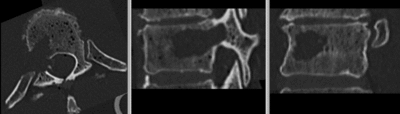

• two images have very different spatial origins (as defined in original DICOM header): recenter first

• the baseline container contains the vertebra upside down (as apparent from orientation of the pedicle/roots of the vertibral arches coming out of the body, visible in sagittal or coronal view). Hence this image needs to have its z-axis (IS) reversed before registration

• the containers walls and lid contain dominant image content that would prevent a successful automated registration; cropping is required

3. Scroll through sagittal view and note the inverted axis orientation